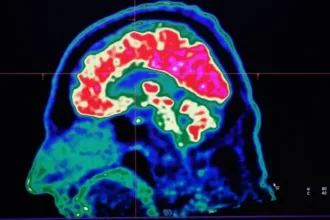

Há condições neurológicas que são agravadas pelo aumento da temperatura GETTY IMAGES…